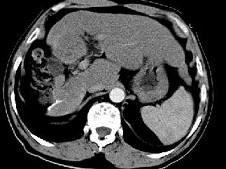

问题 女性,56岁,腹胀、双下肢浮肿、乏力、食欲不振,影像所见如下图,最佳的诊断是 ( )

选项 A.酒精性肝硬化并肝血管瘤 B.血吸虫肝硬化并肝癌 C.肝炎后肝硬化并肝癌 D.局限性脂肪肝 E.原发性肝癌

答案 B